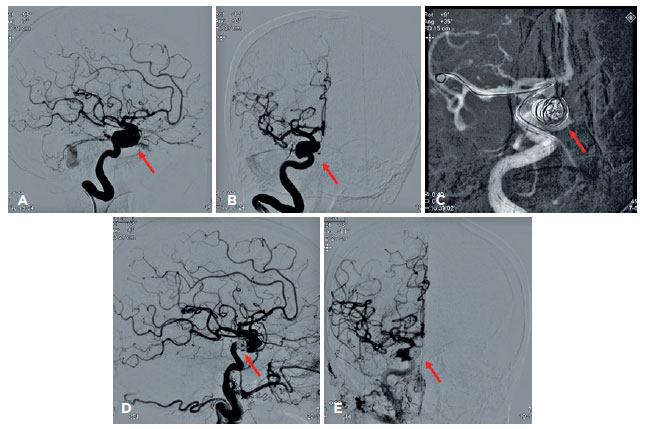

The patient received contrast tomography of the orbit, which revealed dilatation of the superior ophthalmic vein, while arteriography revealing a ruptured saccular aneurysm in the intracavernous portion of the right internal carotid that induced an arteriovenous fistula of the CS (Figure 3A-B). Together with the Neurology and Interventionist Radiology team, it was decided to perform endovascular closure of the fistula (Figure 3C). Anomalous communication was successfully treated (Figure 3D-E), which reduced the eyelid edema and chemosis (Figure 4). Even with treatment, however, corneal edema, hyphema, and vitreous hemorrhage were (4+/4+) on ocular ultrasound, and RE UCVA decreased to near complete absence of light perception. At a 3-month follow-up examination, there was partial improvement of corneal edema and hyphema but no improvement in VA.

11-fig03tb.jpg)